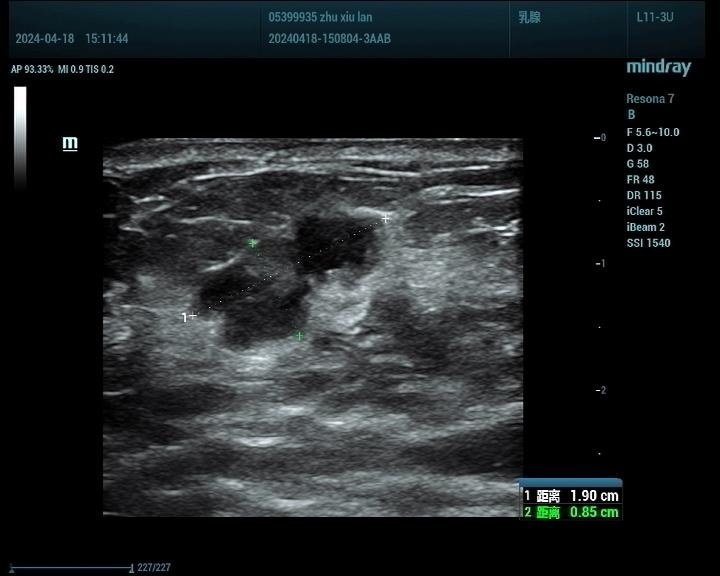

乳腺癌病例